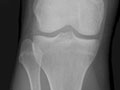

Extremity X-Ray

Test Overview

An extremity X-ray is a picture of your hand, wrist, arm, foot, ankle, knee, hip, or leg. It is done to see whether a bone has been fractured or a joint dislocated. It is also used to check for an injury or damage from conditions such as an infection, arthritis, bone growths (tumours), or other bone diseases, such as osteoporosis.

• Find changes in your bones caused by conditions such as an infection, arthritis, bone growths (tumours), osteoarthritis of the hip, osteoarthritis of the knee, or other bone diseases.